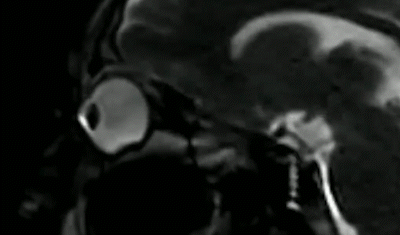

飞进眼里的脏东西最后都去哪了眼睛里进东西时,很多人下意识会揉揉眼睛,揉眼睛不仅会伤到眼球,还会使眼皮随着时间的推移而失去弹性。如果手指不小心碰到角膜,或将眼睛里的异物揉入结膜囊,可能导致角膜上皮损伤。角膜上皮损伤后虽然可以修复,但缺少角膜上皮保护的角膜容易遭受病菌的侵犯。在核磁共振影像下,揉眼睛时的眼球变化是这样的↓↓